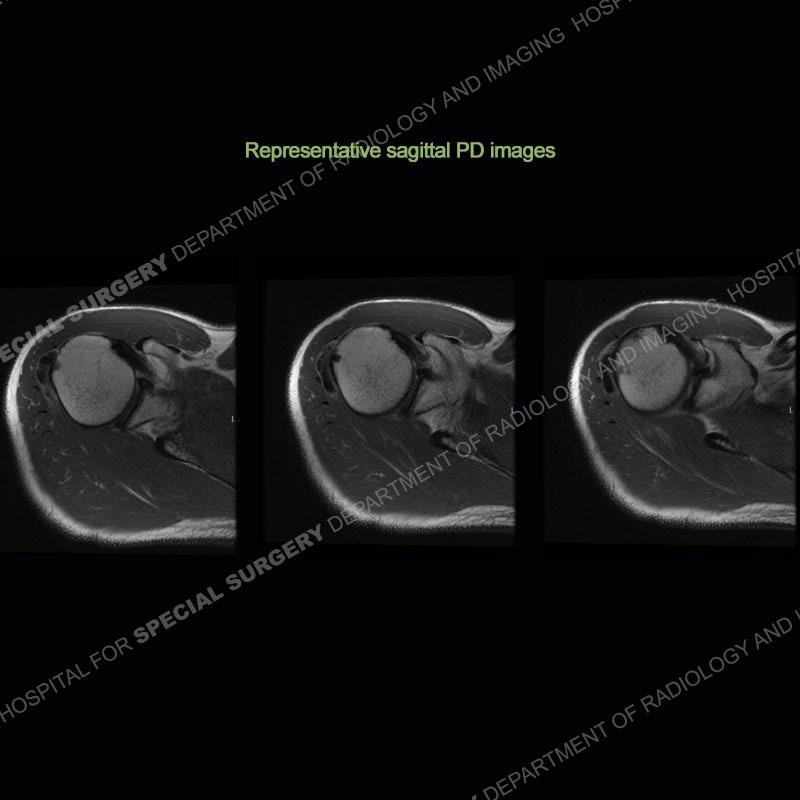

In all cases there are amorphous areas of calcification about the shoulder girdles with varying degrees of density. Varying degrees of edema are seen in the soft tissues on the corresponding MRI examinations. Particularly in case 2, well seen is a change in the density of the calcification from dense to markedly less dense on the radiographs. On the later MRI of case 2, the areas of calcification look almost “liquefied” with surrounding prominent edema in the soft tissue.

On imaging, the calcification becomes less dense and may have a “liquefied” appearance on MRI. On MRI, there is often a marked degree of edema accounting for the patient’s symptoms. Following this, some patients go into a late stage or post calcific stage where there may be some or no pain. Most situations can be treated with oral medication, injection, and aspiration. Occasionally, surgical intervention becomes warranted.